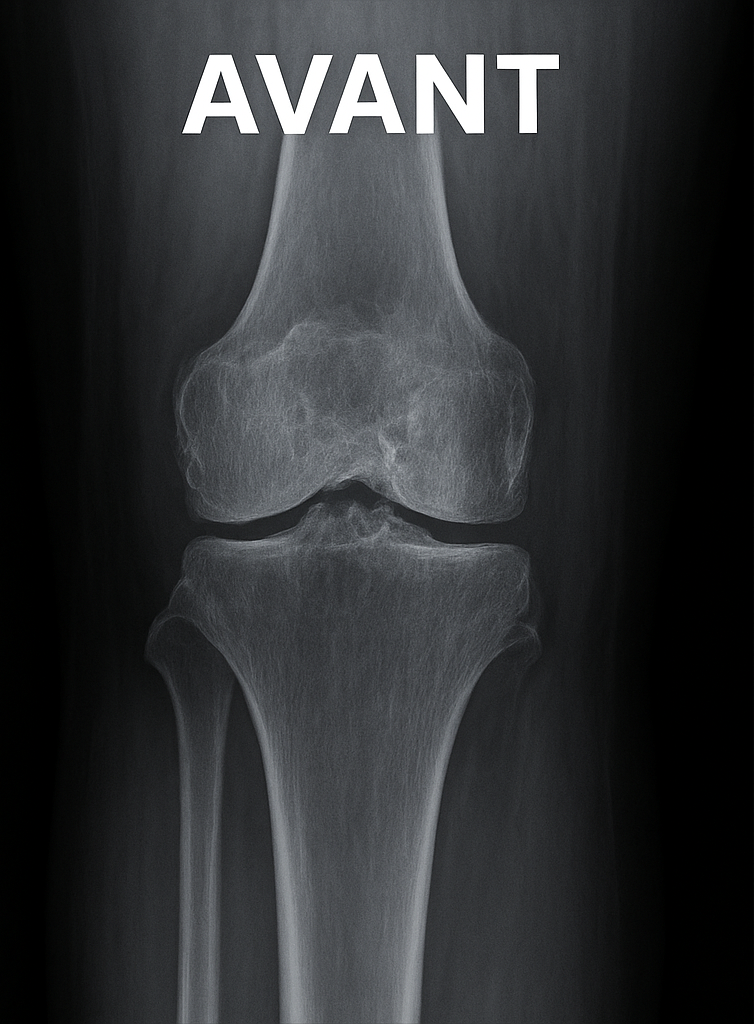

Illustration radiologique

Prothèse du genou